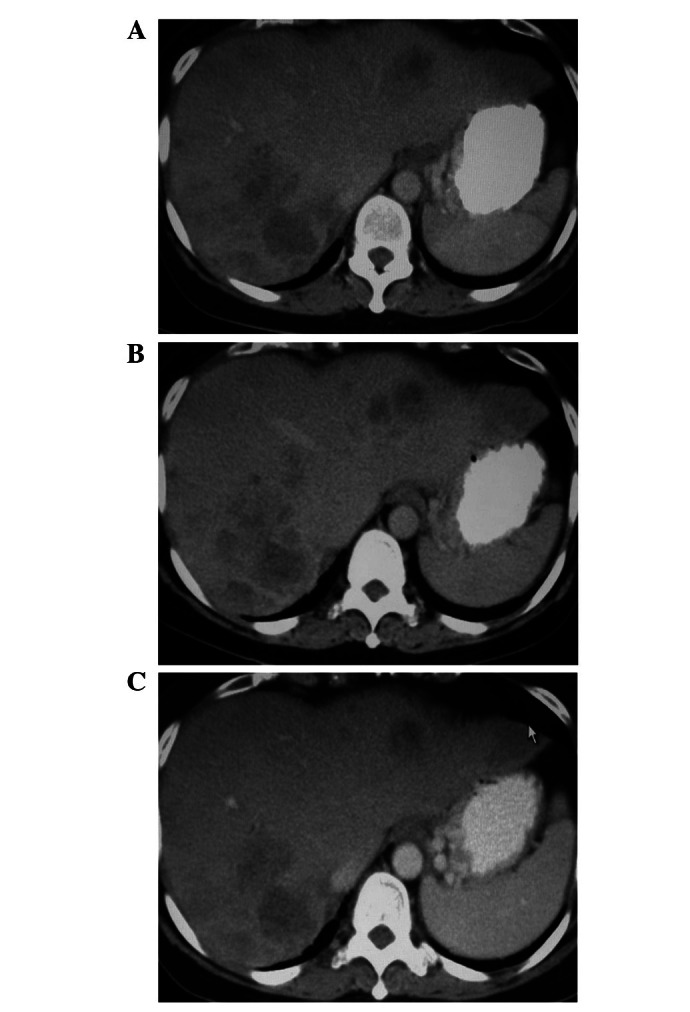

2008 年 5 月,一名 50 岁女性被诊断为结肠癌 IV 期,KRAS 基因发生突变。CT 扫描显示肝脏存在转移的恶性肿瘤,癌胚抗原(CEA)水平为 500 U/ml。患者先后经历化疗、放疗、靶向治疗等,但都无法控制病情,由于无法耐受化疗副作用,最终选择免疫细胞治疗,包括 NK 细胞、CTL(细胞毒性 T 淋巴细胞)。

在第 3 次和第 6 次输注后进行肿瘤评估,CT 扫描表明,结肠和肺部的病变保持稳定,肝转移的肿瘤明显缩小。